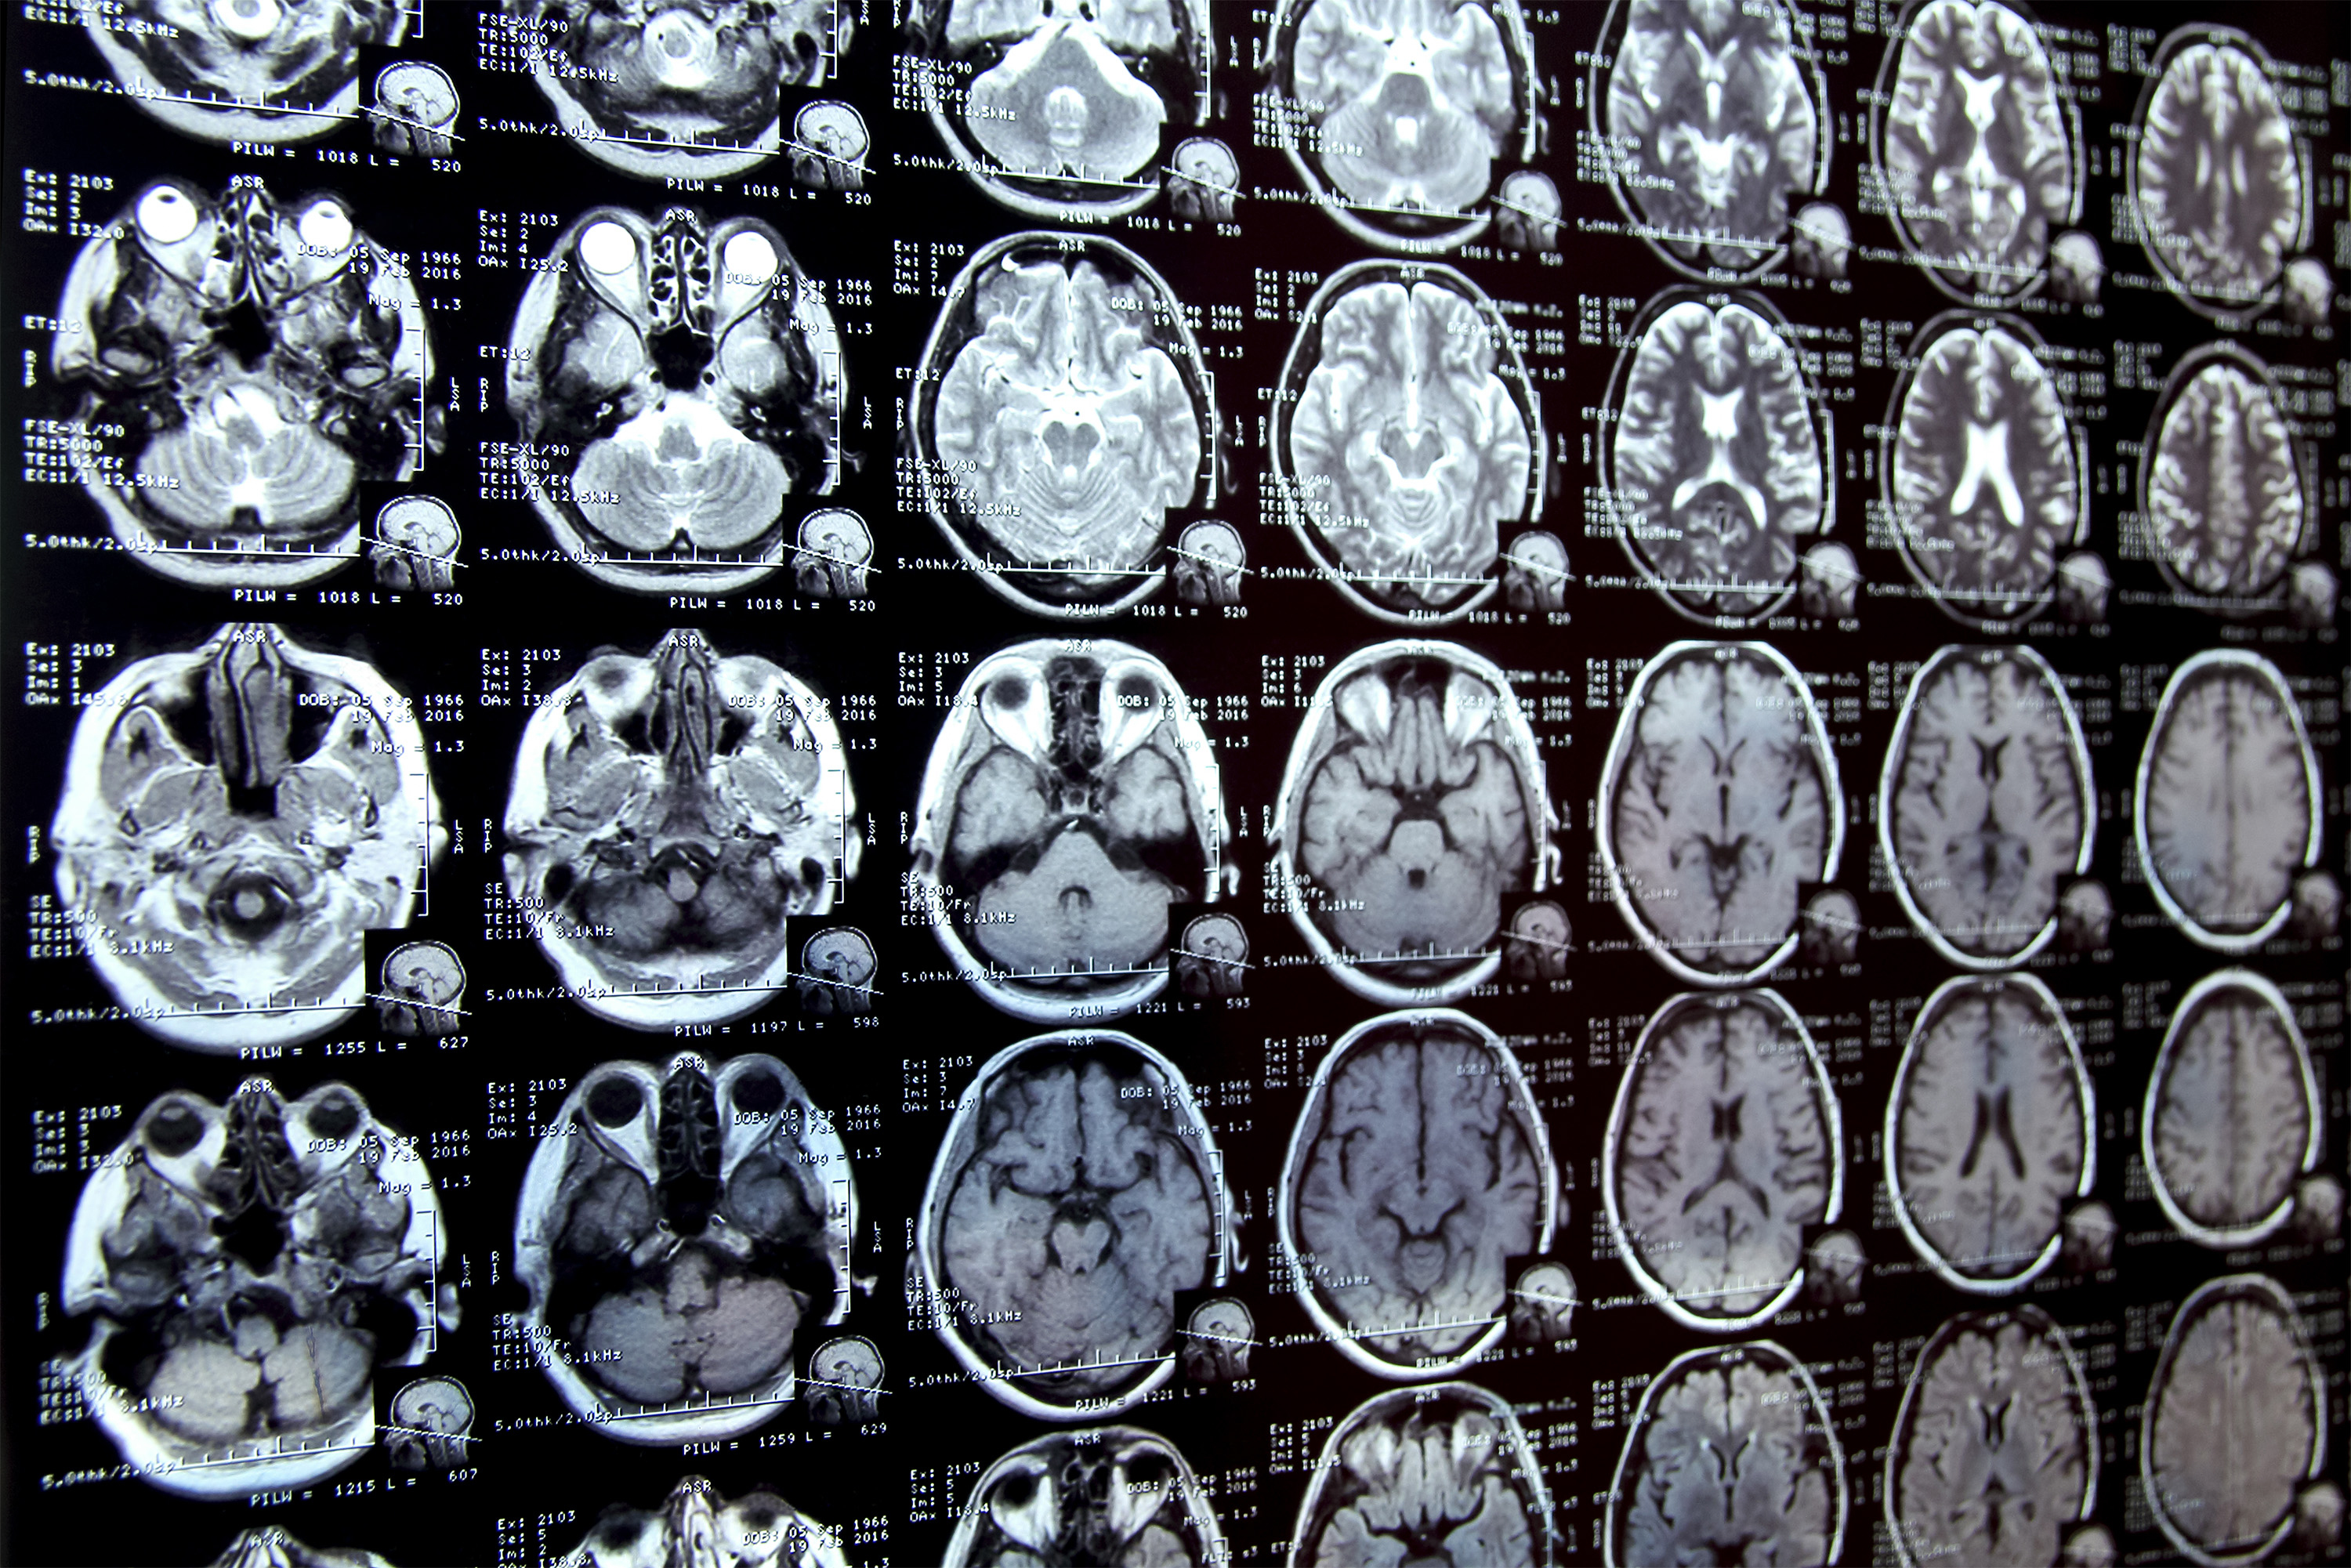

Annotating regions of interest in medical images, a process known as segmentation, is often one of the first steps clinical researchers take when running a new study involving biomedical images.

For instance, to determine how the size of the brain’s hippocampus changes as patients age, the scientist first outlines each hippocampus in a series of brain scans. For many structures and image types, this is often a manual process that can be extremely time-consuming, especially if the regions being studied are challenging to delineate.

To streamline the process, MIT researchers developed an artificial intelligence-based system that enables a researcher to rapidly segment new biomedical imaging datasets by clicking, scribbling, and drawing boxes on the images. This new AI model uses these interactions to predict the segmentation.